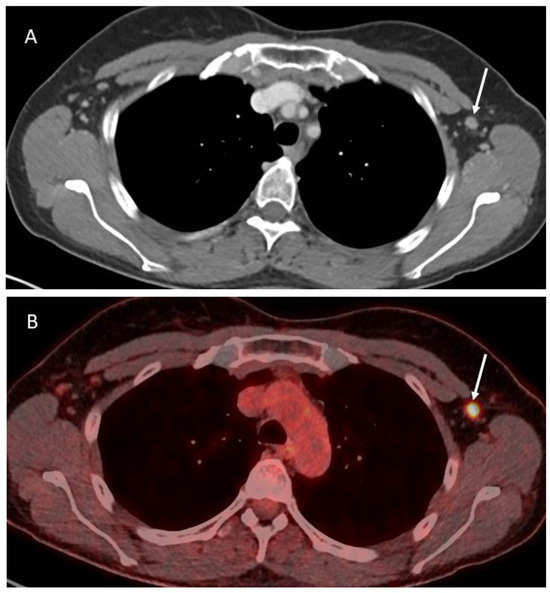

3.2. Imaging

4.2. Imaging

5.2. Imaging

| Axilla | X | X | X | X | Given the superficial position, US is the best imaging modality for assessment of these LN and to guide biopsies | Surgical procedure performed as for breast cancer. |

| Pericardiophrenic fat | X | X | X | Refer to node-RADS [17] for CT and MRI criteria of malignancy. PET-CT more accurate. | Frequently approached through a trans-diaphragmatic approach from the abdomen. In case of difficult exposure, minimally invasive thoracic approaches can be adopted. |